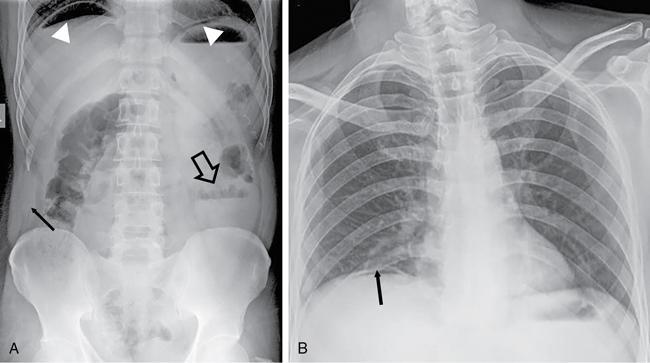

UNDERSTANDING THE ADULT ABDOMINAL RADIOGRAPH: TECHNIQUES AND INTERPRETATION Tanvi Modi Radiography of the abdomen is a common practice for the evaluation of abdominal organs. The anatomy and pathology of digestive, hepatobiliary and genitourinary systems can be assessed using radiographs, either as a stand-alone practice or as a primary imaging modality followed by contrast studies, ultrasound or cross-sectional imaging. In addition, abnormalities of the musculoskeletal or integumentary system can also be deduced on the basis of abdominal radiographs. This chapter intends to give an overview on the techniques and positioning in abdominal radiography as well as interpretation of normal and abnormal features. While superior imaging modalities such as ultrasound, computed tomography (CT), magnetic resonance imaging, capsule endoscopy and the likes have taken over abdominal imaging by and large, radiography still holds a pivotal role in certain situations and conditions, such as: The standard abdominal radiograph is taken in supine position and anteroposterior projection. This is also popularly known as the KUB (kidneys-ureters-bladder) radiograph. Previously, supine as well as erect radiographs were performed in all patients; however, this is not commonly done due to high-radiation dose. For all indications of abdominal radiography, including acute abdomen, supine radiographs are sufficient in terms of radiographic diagnosis, with the exception of perforation for which an erect chest or lateral decubitus radiograph can be performed if there is clinical suspicion. Patient should lie supine on the imaging table with median sagittal plane at right angles to the table and coincident with the midline of the table (Fig. 7.1.1.1). The body is divided into equal right and left halves by the median sagittal which passes through the sagittal suture of the skull. Pelvis should be adjusted so that the anterior superior iliac spines are equidistant from the table top. Gonadal shields, in the case of male patients, should be placed with the upper edge of the shield at the level of pubic symphysis. Although rarely used for female patients, these should be positioned between the anterior superior iliac spines and the pubic symphysis. The centre point of the image receptor should be approximately located at a point 1 cm below the line joining the iliac crests. The X-ray beam should be in a vertical direction, perpendicular to the table top and image receptor at the centre point. Collimation should be such that the soft tissue and subcutaneous region along lateral aspects of the abdominal cavity should be covered within the image. Also, the superior extent involving diaphragm and inferior extent involving the inferior pubic rami is important to look for any lower chest pathologies or any inguinal hernia. 35 × 43 cm (14 × 17 inches) in portrait orientation. On an average, abdominal radiograph exposes a patient to a dose of approximately 1.5 mSv, which is equivalent to 75 chest radiographs or 1/6th dose of a standard CT of the abdomen. The entrance skin dose is approximated to be 4 mGy. At such an effective dose, the additional lifetime risk of fatal cancer is 1 in 30,000. The exposure time is kept short. Patient is asked to exhale completely and hold their breath, with exposure taken at this point of full expiration to ensure imaging of abdominal organs in their natural positions. Modifications of this technique can be made depending on patient habitus and clinical condition. Kilovoltage peak (kVp) should be set to allow adequate visualization of abdominal soft tissue structures as well as semiopaque renal and biliary calculi. Average kVp is set at 70–85 kV. 102 cm (40 inches) Grids are commonly used to reduce scatter radiation. Placement of side marker on the image receptor at the time of radiographic exposure is essential. Bowel pattern depiction should be such that there is minimal lack of sharpness. Standard guidelines for abdominal radiography dictate that the radiograph should extend from the diaphragm up to the level of inferior pubic rami and must include the lateral abdominal wall musculature. The abdomen is divided into four quadrants on the basis of two perpendicular lines (Fig. 7.1.1.7). The vertical line passes through the mid sagittal plane and crosses the umbilicus and symphysis pubis. The horizontal line is a transverse line across the umbilicus at 90 degrees to the vertical line and is situated at the level of L4–L5 intervertebral disc. The quadrants are as follows: Another division system is dividing the abdominopelvic cavity into nine regions using two vertical and two horizontal planes (Fig. 7.1.1.8). The vertical planes, also known as the right and left lateral planes, are parallel to the midsagittal plane between midline and anterosuperior iliac spines on either side. Of the two horizontal planes, the upper transpyloric plane is at the level of lower border of L1 and the lower transtubercular plane is at the level of L5. The nine regions are: On a standard radiograph, the exposure should be such that the stomach, bowel loops, outlines of liver, spleen, kidneys, psoas muscles should be well identified. Also, lumbar transverse processes should be seen. Arch of the pubic symphysis should be visible to evaluate bladder region. A well-centred film without rotation will demonstrate bilaterally symmetrical lower ribs, iliac wings, ischial spines and obturator foramina. Different structures seen on an abdominal radiograph can be classified into five basic densities: Identification of different structures depends on the relative degree of contrast between their densities. The demarcation is clearer in chest and is diminished in abdomen due to relative similar soft tissue density of various structures. On a normal radiograph, relatively large amounts of gas in stomach and colon with minimal small bowel gas can be seen. Further, colonic gas can vary from negligible to extensive, mimicking obstruction pattern; however, usually the gas is enough to delineate colonic haustral pattern. Faecal matter gives a mottled appearance to colonic gas. Short-air fluid levels on an erect radiograph may be seen even in normal cases. The normal appearance of small bowel loops on an abdominal radiograph follows the rule of threes: Stomach is seen in the left upper quadrant and is visualized when distended with air. It is commonly seen extending from T11 to L2 level. Common feature identifying the stomach is the fundal gas which is usually seen as an air fluid level within the gastric lumen. Small bowel loops are distributed to the centre of the abdominal cavity and large bowel loops are peripheral. Duodenum is predominantly situated in right upper quadrant. It extends to left upper quadrant in the region of duodenojejunal flexure. Jejunum occupies the left upper and lower quadrants and is easily identified due to the presence of thick, numerous, closely spaced valvulae conniventes (Fig. 7.1.1.9A). The ileum occupies both lower quadrants and extends into right upper quadrant. Ileum has few and less prominent valvulae as compared to jejunum (Fig. 7.1.1.9B). Ascending and descending colon are retroperitoneal and have relatively fixed positions along lateral aspect of the abdominal cavity on either side. Transverse and sigmoid colon, on the other hand, may have a variable position due to their mobility along mesocolon and redundant pattern. These can be identified with confidence on account of haustrations and faecal matter (Fig. 7.1.1.10). Haustrations are usually well seen in ascending and transverse colon and poorly delineated beyond splenic flexure. Caecum is in the right lower quadrant, though it may be mobile or pulled up. Rectal gas is usually seen in the midline at the level of pelvis and its presence rules out large bowel obstruction. All these positions may vary due to anatomical conditions such as malrotation or pathological conditions, for example volvulus. Liver, spleen and renal outlines cannot be completely traced with precision due to the overlap by bowel loops. On a frontal projection, the liver appears as a triangular structure occupying right and left hypochondrium and epigastric region. Occasionally, the right lobe may be seen extending lower than the right renal shadow. This is a normal variant known as Reidel’s lobe. Gall bladder is situated in the posterior and inferior region of the liver and any pathology of the gall bladder should be looked for in this region. On a lateral radiograph, the gall bladder is anterior to the midcoronal plane. This helps in distinguishing gall bladder calculi from renal calculi, which will be more posteriorly situated. Spleen is seen in left upper quadrant/left hypochondrium, flushed to left lower ribs and left hemidiaphragm. Pancreas is present in the epigastric region (right and left upper quadrants) and is usually not identified in the absence of a pathology. The kidneys are bean-shaped retroperitoneal organs which are seen on either side of the vertebral column and lateral to psoas muscles. Due to the presence of liver on the right side, this kidney is slightly lower in position as compared to its contralateral counterpart. The visualization of kidneys on radiographs is facilitated by the surrounding fatty capsule. Kidneys lie between T11–12 and L2 level, with left kidney 1 cm higher than the right. Psoas muscle shadow can be normally seen along lateral aspect of lumbar spine bilaterally and is mildly concave (Fig. 7.1.1.11). Abdominal wall muscles are not routinely assessed on radiography; however, inclusion of lateral abdominal wall (muscles as well as subcutaneous plane) is a must while performing radiography. The flank stripe or the properitoneal fat stripe is a fat density linear concavity seen along lateral abdominal wall (Fig. 7.1.1.11). It is bound by the paracolic gutters and air-filled ascending and descending colon. All the solid organs in the abdomen are identified due to the fat density outlining them. Distortion of these fat lines helps in identifying organomegaly or focal mass lesions. The dome of urinary bladder is outlined by fat, which aids in differentiating its density from other soft tissue structures of the pelvis. Not all calcifications seen on abdominal radiograph are abnormal. Some may depict age-related changes such as vascular calcifications involving abdominal aorta, pelvic vessels, splenic artery in the region of left upper quadrant. Within the pelvis, phleboliths may be seen and mistaken for urinary calculi. Assessment of lumbosacral spine, iliac bones and femoral heads can be made on the basis of plain radiography. Degenerative changes may be commonly seen. Lower ribs can also be evaluated for pathologies. Dilated small bowel loops with rounded soft tissue density in midline over umbilical region suggests obstruction secondary to umbilical hernia. Pneumoperitoneum must be looked for in all cases of acute abdomen. While erect chest and left lateral decubitus radiographs can detect even 1 mL of free air, there are multiple signs on supine radiograph to suggest this diagnosis, for example Rigler’s sign, falciform ligament sign, football sign (Figs. 7.1.1.24 and 7.1.1.25). Retroperitoneal perforation may demonstrate air outlining psoas muscles and retroperitoneal organs. Small amount of free air may persist in the abdominal cavity up to 3 weeks after surgery, although it usually resolves within a week. Clinical history is important in such cases. Air foci within the bowel wall may represent bowel ischaemia/strangulation. Linear gas patterns in right hypochondrium may be due to two causes, that is pneumobilia and pneumoporta. The former can be seen normally postbiliary surgery, sphincterotomy, ERCP or in the case of abnormal fistulous communication between bowel and biliary tree (Fig. 7.1.1.26A). Pneumoporta (Fig. 7.1.1.26B) is a red flag and warrants further investigation to look for conditions such as mesenteric ischaemia and toxic megacolon. Pneumobilia is more centrally located whereas air shadows in pneumoporta are seen reaching up to periphery of liver. Air foci over renal shadows (Fig. 7.1.1.27), gall bladder or pancreas, in the absence of recent procedural history, suggest fulminant infection and mandate urgent intervention. Central midline calcific foci between T9 and T12 vertebrae can be attributed to calcific pancreatitis (Fig. 7.1.1.28). In the left upper quadrant, areas of calcification seen involving a shrunken spleen may be seen in autosplenectomy. In right upper quadrant, calcified gall stones may be seen. These tend to be small, multiple, uniformly circumscribed and ring-like in appearance with central translucency (Fig. 7.1.1.29A). Mercedes Benz sign, a triradiate pattern of gas lucency, is associated with gallstones. In contrast, renal calculi are more commonly solitary, irregular, of homogenous density, conform to renal calyceal or pelvic outline (Fig. 7.1.1.29B) and are sometimes of staghorn configuration. On lateral view, the gall stones are more anteriorly located as compared to renal calculi, which may be partly superimposed on lumbar vertebrae. Ureteric calculi tend to overlap bony structures such as lumbar transverse processes (Fig. 7.1.1.29B) or sacroiliac joints. Extensive or patchy, curvilinear calcification of gall bladder wall is known as porcelain gall bladder which is often associated with malignant transformation. Calcification involving adrenal glands may be secondary to infection or haematoma, or a congenital condition known as Wolman’s disease where there is bilateral involvement. Discontinuous discrete midline tram track calcification in the abdomen may indicate atherosclerotic changes in abdominal aorta and branch vessels. However, when the calcification is in a globular pattern and seen below the level of L2 vertebra, aortic aneurysm should be suspected (Fig. 7.1.1.30). Appendicoliths, though not commonly seen, may sometimes be detected in right iliac region. Pelvic calcifications: vesical calculi, distal ureteric or vesicoureteric junction calculi, calcified fibroids, ovarian dermoid with tooth-like calcifications (Fig. 7.1.1.31) may be the cause of abdominal pain and should be diligently looked for. Vesical calculi are usually more large and central in location whereas calcification due to fibroids may be more lateral. Schistosomiasis is another cause of bladder wall calcification, as is calcification of bladder tumours. Phleboliths tend to be bilaterally symmetrical, with a lucent centre unlike ureteric calculi. While it is believed that phleboliths are located below the level of ischial spines and ureteric calculi above, this is not always true and should be confirmed with CT. Fluid may collect adjacent to properitoneal fat line, forming a linear soft tissue density separating the fat line from the ascending or descending colon. Hellmer’s sign demonstrates medial displacement of lateral edge of liver (hepatic angle), due to fluid collection or ascites. Gross ascites may appear as generalized abdominal haziness or diffuse increased density of pelvis. Abscesses can involve any solid organ and in such cases may be difficult to demonstrate on plain radiography alone. Enlargement of organ or faint gas densities within can be suggestive of the same. In the case of peritoneal abscess, mottled density due to air, fluid and necrotic contents point towards this diagnosis, especially in right iliac fossa in association with appendicitis. Retroperitoneal abscess, similar to any retroperitoneal mass, may cause displacement of retroperitoneal structures (Fig. 7.1.1.32). Subdiaphragmatic abscesses may show concomitant ipsilateral pleural effusion (Fig. 7.1.1.33). These should be differentiated from Chilaiditi syndrome. Fluid and soft tissue lesions present with the same density on radiographs. While it is difficult to characterize the lesion and organ of origin, clues for the same can be provided by organomegaly (Fig. 7.1.1.34), distortion of fat surrounding solid organs, displacement of bowel loops or solid organs. For example, a retroperitoneal lesion may cause anterior or inferior displacement of kidney, a pelvic mass may cause upward displacement of small bowel loops. Different densities such as fat or calcification may help in identifying organ of origin (e.g. fat and tooth densities seen in ovarian dermoid). Convexity of margins of psoas muscle on an abdominal radiograph can be due to haematoma, abscess or intramuscular tumour. Radiographs are performed for the initial diagnosis of foreign body in the abdomen including type, number of foreign bodies, location, size and shape (Fig. 7.1.1.35). Radiolucent foreign bodies such as wood, plastic, chicken bones will not be easily identified on radiography. Low kVp (65–70 kVp) can increase contrast and help identify these objects. In addition to an abdominal radiograph, chest radiography is also performed to exclude aspiration or oesophageal location of foreign body. Ingested or introduced foreign bodies may cause complications such as obstruction, perforation, fistula formation and sepsis. Hence, once their presence is confirmed, follow up radiography must be performed until they are eliminated. One must look for fractures/dislocation injuries involving the vertebrae or pelvic bones, especially after history of trauma. Lucent expansile lesions or sclerotic bony deposits which represent neoplasms, absent pedicle sign in cases of metastasis, metabolic bony changes such as rugger jersey appearance, Paget’s disease, arthropathies such as ankylosing spondylitis with bamboo spine appearance and sacroiliitis (Fig. 7.1.1.36) are some of the conditions which may be diagnosed based on an abdominal radiograph. Overlap of bowel loops over iliac blades may lead to a misdiagnosis of lucent lesions and should be evaluated with caution. Basal pneumonia may be the cause of acute abdominal pain and should be looked for in abdominal radiography. Similarly, pleural effusion, pericardial effusion, calcified pleural plaques, achalasia, interstitial fibrosis are few other findings that can be seen in lower chest on an abdominal radiograph. Basilar atelectasis can give a deceptive appearance of pneumoperitoneum (Fig. 7.1.1.37). Surgical clips, commonly in right hypochondrium after cholecystectomy, drainage tubes, ventriculoperitoneal shunts, femoral line catheters, IVC filters, stents (vascular, renal, biliary) (Fig. 7.1.1.38), stoma bags, contraceptive devices are some structures that may be seen in an abdominal radiograph. Correct knowledge of patient history and normal locations of these structures prevents misdiagnosis. Certain artefacts may be projected upon the radiograph due to surface structures such as trouser buttons, body piercing, sequins over clothing and should not be considered as a pathology. Multiple skin surface nodules in cases of neurofibromatosis, soft tissue focal swellings, such as abscesses, lipomas, haematomas, desmoid tumours and malignant lesions may be incidentally seen on radiography. These can be further evaluated using ultrasound or CT. Subcutaneous emphysema is another finding that may be seen in lower abdominal wall secondary to retroperitoneal perforation or diffusely along abdominal wall in the case of bowel perforation (Fig. 7.1.1.39). Foreign bodies such as bullets and pins may be seen lodged in abdominal wall. A systematic approach to abdominal radiographs is important for accurate diagnosis as follows: Despite the development of newer techniques for imaging of the abdomen, plain radiography still holds an important place in the initial assessment of acute abdomen. Positive and negative findings on an abdominal radiograph can direct further investigation. Ideal positioning, recognition of normal appearances and keen scrutiny for pathologies is a sine qua non for radiologists reading a plain film of the abdomen. OESOPHAGOGRAM Padma V. Badhe, Vikram Reddy, Sultan Moinuddin Shaukatali, Zillani Alam, Ravi Varma, Abhishek Bairy, Dasari Ravikiran, Revati Tekwani, Soniya Patankar, Megha Nair, Gautham Shankar Oesophagogram is the process of obtaining radiological images and simultaneous motion recording to evaluate function and disorders of pharynx, oesophagus and proximal stomach. Oesophagogram is usually done primarily to evaluate dysphagia. Some of the common indications are oesophageal motility disorders, strictures, gastro-oesophageal reflux disease (GERD) and suspected masses. It can also be used to detect uncommon anomalies like vascular rings/slings and aberrant anatomy. It also helps to evaluate further in cases where there is inability to pass upper GI scope. Double-contrast oesophagogram is mainly indicated in early mucosal disease like erosion, polyp, infection and tumours. If a motility disorder is suspected, dynamic technique (e.g. videofluoroscopy) is used for dysphagia or aspirations in cases of stroke, neuromuscular disorders, post head and neck surgery or radiation. Barium oesophagogram is contraindicated in suspected cases of perforation and tracheoesophageal fistula, aspiration, rarely if there is hypersensitivity to barium suspensions. It is also contraindicated in suspected oesophageal perforation where a water-soluble contrast agent is more suitable. However, ionic water-soluble contrast agent is better avoided in cases of aspiration or fistula with airway. The contrast examination of the pharynx is dangerous in cases of acute epiglottitis and must be ruled out on plain radiograph. An 80% w/v barium suspension is used in full column views. However, 200%–250% w/v barium suspensions is usually required for mucosal relief films. The barium sulphate mixture is fed to the patient either by spoon, by glass, or through a drinking straw, depending on its consistency. In videofluoroscopy, the pharyngeal phase of swallowing is usually safer with barium pudding than with thick barium and safer with thick barium than with thin barium. However, if the major abnormality is poor pharyngeal contraction leading to stasis in the piriform sinus (and epiglottic tilt is normal), a thin liquid is safer. Epiglottic motility is better assessed with thin barium because thick barium often obscures the epiglottic tip. Fluoroscopic equipment capable of cine fluoroscopy and capability for rapid sequence spot images (high frame rate) is needed for this examination, Barium suspension, straw, glass, Lead apron and radiation protective equipment. The patients are instructed to fast after midnight before the day of the examination. The pharynx should be made as dry as possible during the examination as high-density barium adheres to dry pharyngeal mucosa. Activities like smoking, chewing gum and lozenges must be abstained before the procedure as they impair barium coating by increasing the salivary secretion. Regular oral medications must be taken with sips of water; however, insulin must be skipped on the morning of examination. The major principles of a good oesophagogram includes mucosal coating, distension and projection. A routine oesophagogram consists of screening of the oral, pharyngeal and oesophageal phases of swallowing, single and double-contrast examination of pharynx, single contrast, double-contrast and mucosal relief views of the oesophagus. In cases of dysphagia, the examination is tailored depending on whether the symptoms are either pharyngeal or oesophageal and initial fluoroscopic findings. If patients’ symptoms are suggestive of oral or pharyngeal disorder then pharynx is evaluated first. Similarly, if patient is suspected to have thoracic oesophageal disease then, double-contrast examination of the oesophagus is performed before the pharyngeal evaluation. During an oesophagogram the positioning of the patient varies according to the type of examination (Table 7.1.2.1).